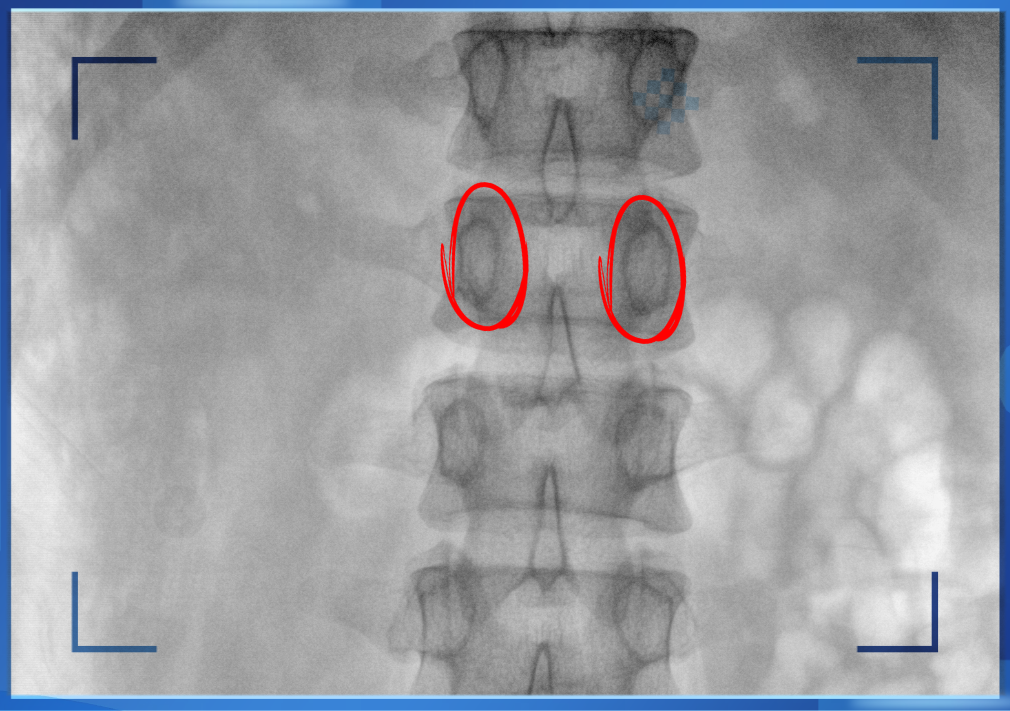

醫(yī)生通常會(huì)在“貓眼”里尋找進(jìn)針點(diǎn)和出針點(diǎn),憑醫(yī)生的經(jīng)驗(yàn)把釘子打在椎弓根里。手術(shù)比較依賴醫(yī)生的經(jīng)驗(yàn),萬一出現(xiàn)偏差對(duì)病人來講就是毀滅性的打擊。如果在復(fù)雜的手術(shù)中有三維影像的支持,確保釘子精準(zhǔn)的打在椎弓根里,可大大的提高手術(shù)操作的精度。

“貓眼”指的是椎弓根在正位的投影。